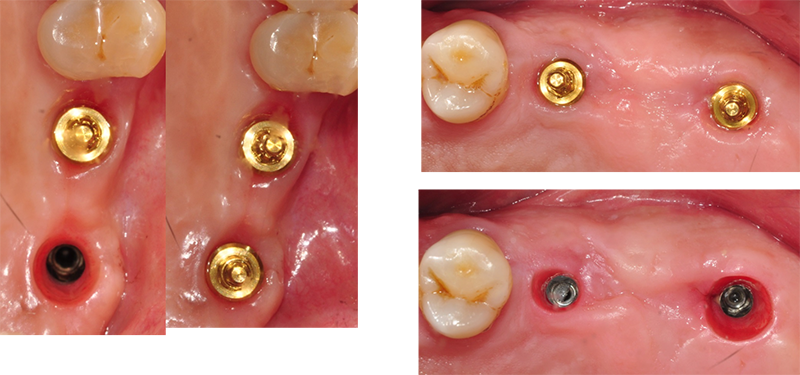

Healing Ab

1-piece

Ab

Convertible Ab(EZC,MUA,Octa 등등)

2-piece Ab

을 철거 했을 때

잇몸 내면의 모습.

Micro-gap or Micro mobility

빨갛게 되거나 피가 나면 안 된다.

Micro mobility가 있으면 발적된 치은을 볼 수 있다.

35N 힘으로 조여진 convertible abutment을 풀어서 빼보면 약간 하얗게 보이는 경우도

있다. 그리고 살짝 찢어지면서 핏방울이 맺히는

양상도 보인다. Hemi-desmosome에 의한 부착이 떨어지면서 나타나는 결과다.

Hemi-desmosome에 의한 부착이 손상 받지 않아야 잇몸 하방에 있는 치조골도 보호가 된다. 절대적 명제로 여기는 것이 좋다.